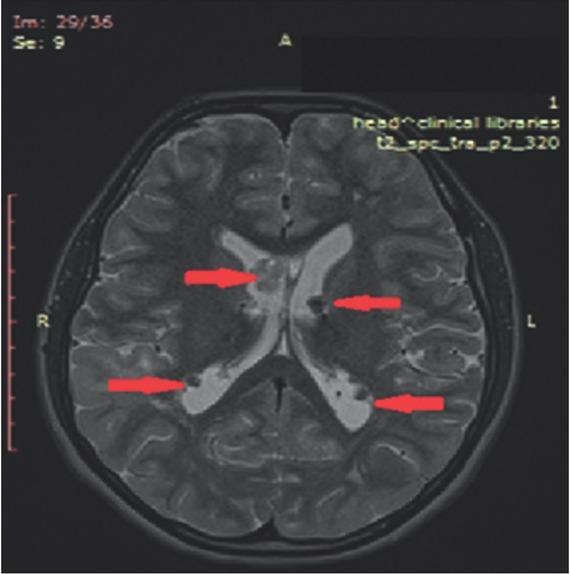

Figure 3